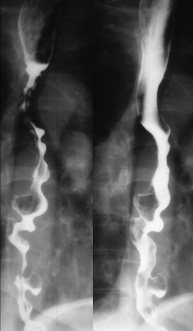

Image TOGD d'une megaoesophage sur

le cliche de face et OAD . Bord lisse et

aperistaltisme ., la retressisement a inferieure est

image en queue de radis |

Megaoesophage en face

et en profile OAD |

A etat tardive oesophage dilate et

alonge en forme de petit chaussette . |